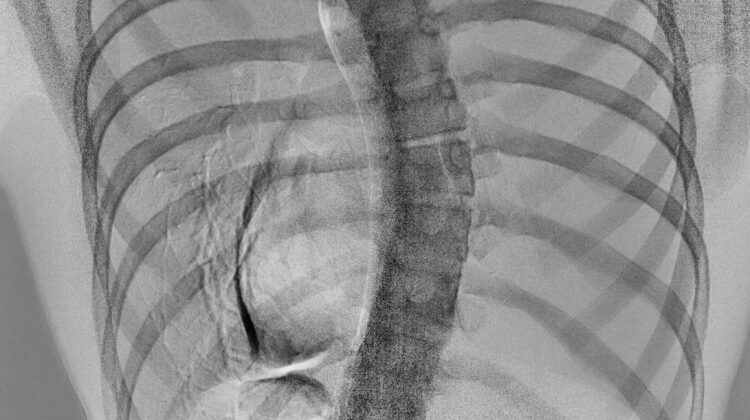

اعوجاج العمود الفقري مجهول السبب، أو الجنف، هو انحناء جانبي للعمود الفقري يظهر غالبًا خلال مرحلة النمو السريع في المراهقة. السبب الدقيق لا يزال مجهولًا، لكن الدراسات تشير إلى أن العوامل الوراثية، قوة العضلات، والتوازن الهرموني والأيضي تلعب دورًا مهمًا في تطوره. الجنف لا يقتصر على الشكل الخارجي للظهر، بل يشمل تغيرات داخلية في العضلات والعظام والفقرات، ما قد يؤثر على استقرار العمود الفقري ووظيفته.

الأيض أو التمثيل الغذائي هو مجموعة العمليات الحيوية التي تحدث داخل الجسم، مثل إنتاج الطاقة، بناء العضلات والعظام، وتنظيم الهرمونات. تشير الأبحاث إلى أن اختلال بعض هذه العمليات الأيضية قد يكون جزءًا من أسباب الإصابة بالجنف، خصوصًا إذا ترافق مع عوامل ميكانيكية مثل الوقوف والمشي على قدمين.

نموذج النمو السريع: في سن البلوغ، يمر العمود الفقري بمرحلة نمو سريع. أي خلل في هرمونات النمو أو الغدة الدرقية قد يغير معدل نمو العظام ويؤثر على التوازن بين الفقرات.

نموذج ضعف تكوين العظام: ضعف تكوين العظام أو نقص المعادن الحيوية يجعل العمود الفقري أقل قدرة على التحمل، ويزيد من خطر الانحناء التدريجي.

حتى الآن، لا يوجد نموذج واحد مثبت بشكل قاطع، لكن من المرجح أن الجنف يحدث نتيجة تداخل عدة عوامل أيضية وميكانيكية وهرمونية.